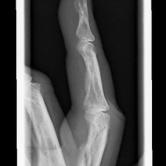

Röntgenbilder